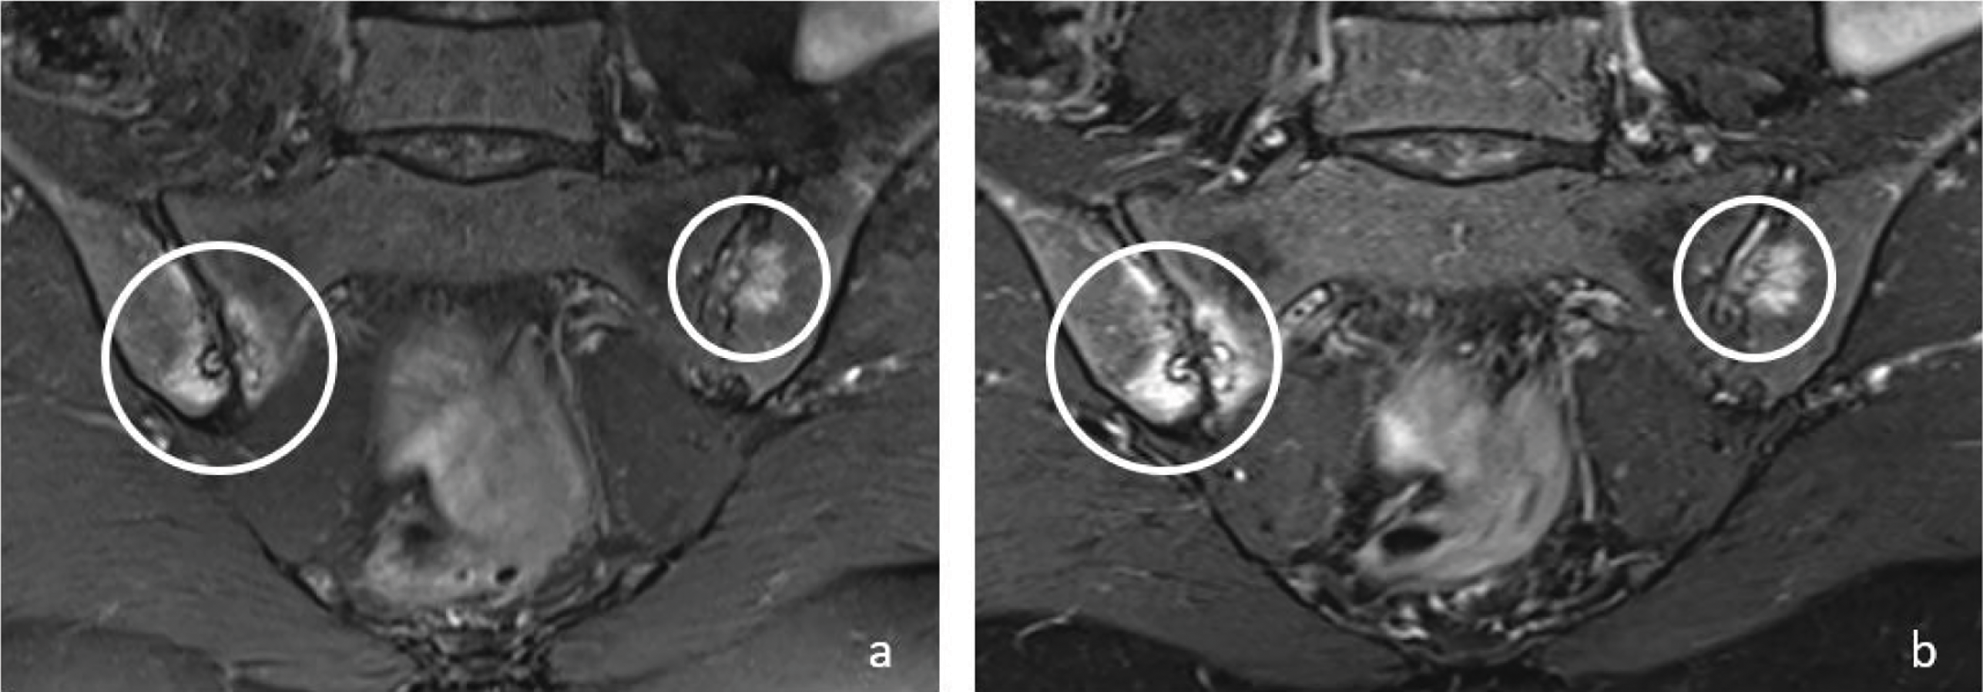

In the evaluation of active sacroiliitis, there was no statistically significant difference between standard FS‑T2W and T2W Dixon WO images in detection of BME (P > 0.05) (Figure 1).

Figure 1

Coronal T2W‑FS (a) and T2W Dixon WO (b) images show bone marrow edema (circles) in both sacroiliac joints on the right sacral and iliac side and on the left iliac side in a 48‑year‑old female patient. Bone marrow edema signals are brighter on T2W Dixon WO images (b).